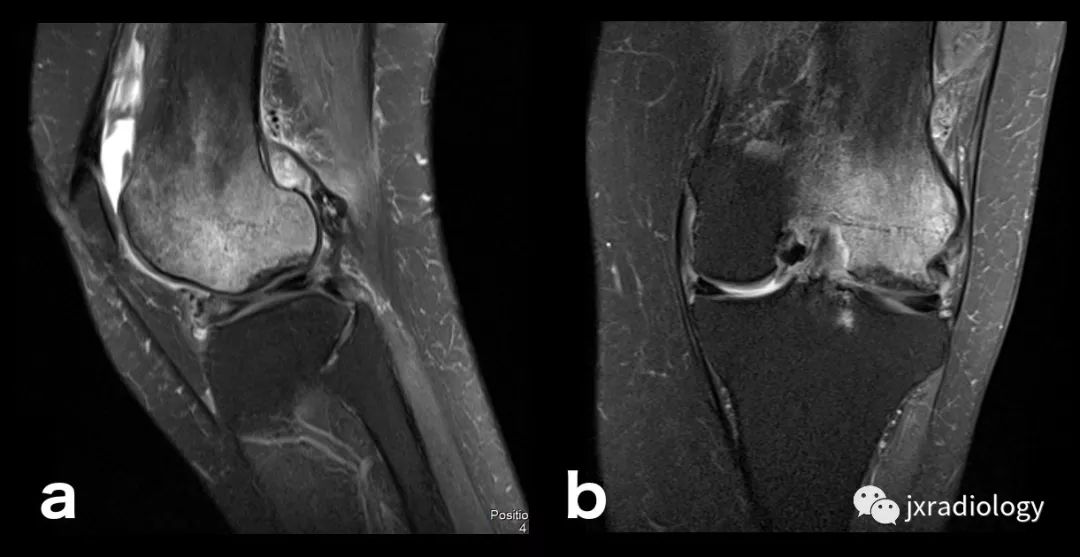

在关节扫描中,大部分fs序列都是扫描间于pdwi与t2wi间的中间权重序列.

fse pdwi-fs

收藏膝关节骨髓水肿影像综述